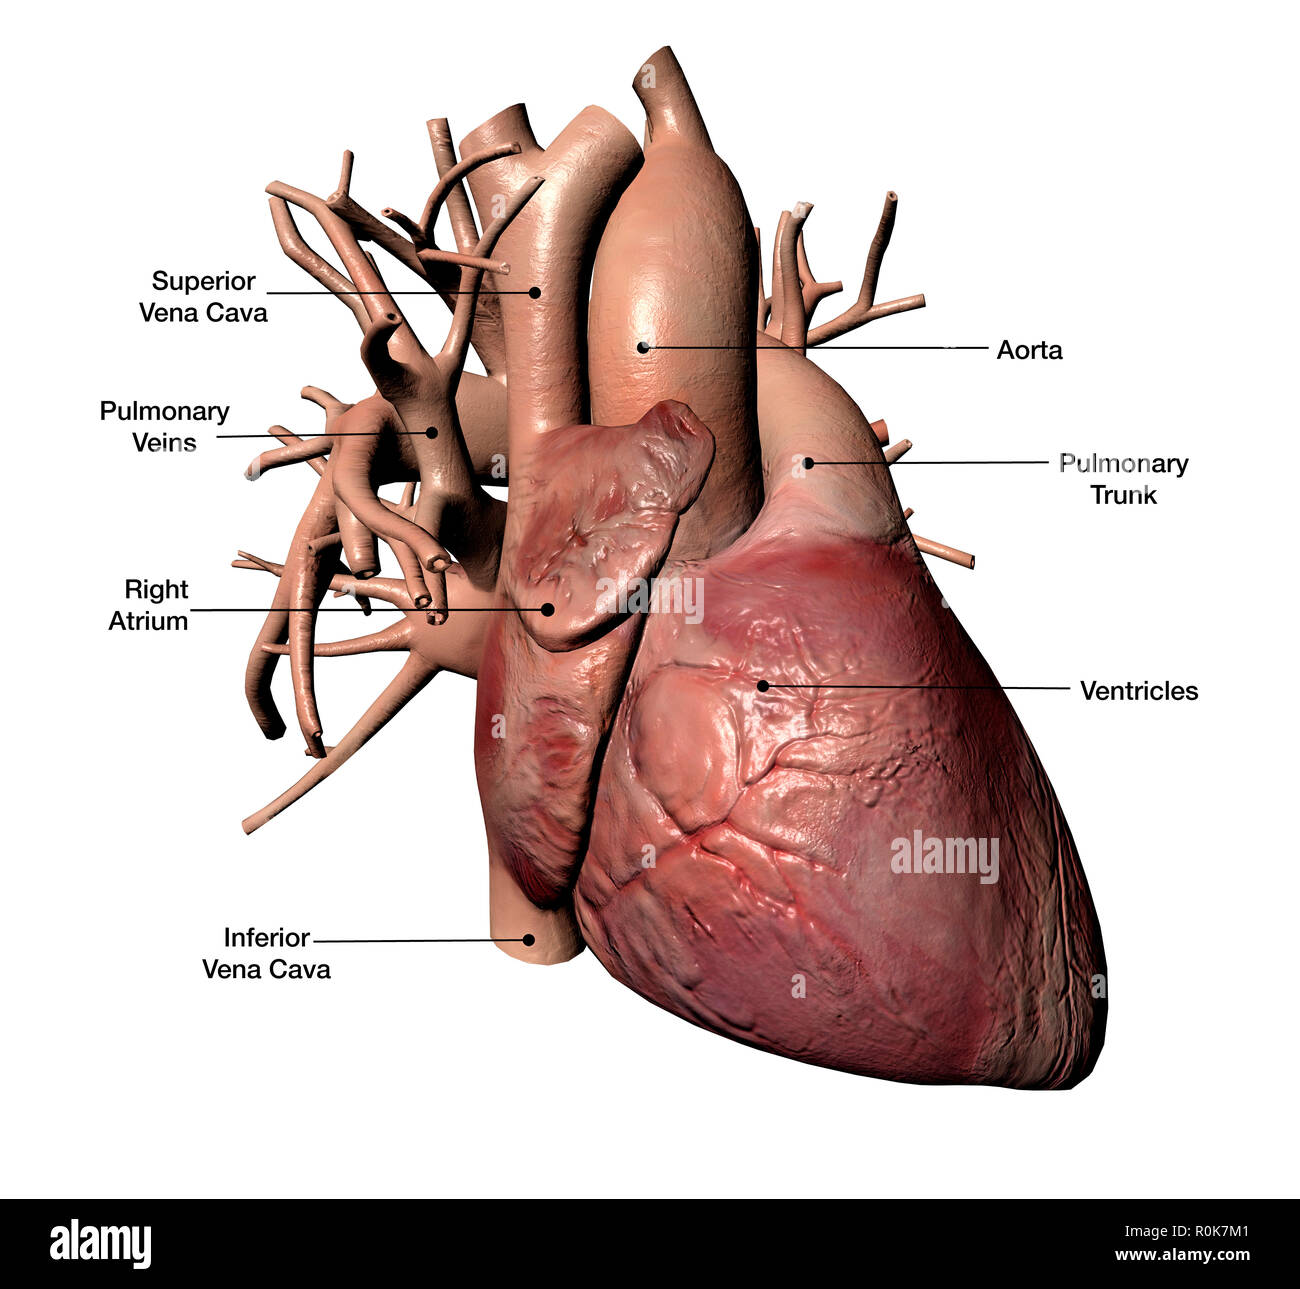

Human heart diagram Cut Out Stock Images

Human heart anatomy close up diagram concept from a healthy body isolated on white background as a medical health care symbol. Stock Photohttps://www.alamy.com/image-license-details/?v=1https://www.alamy.com/human-heart-anatomy-close-up-diagram-concept-from-a-healthy-body-isolated-on-white-background-as-a-medical-health-care-symbol-image255880693.html

Human heart anatomy close up diagram concept from a healthy body isolated on white background as a medical health care symbol. Stock Photohttps://www.alamy.com/image-license-details/?v=1https://www.alamy.com/human-heart-anatomy-close-up-diagram-concept-from-a-healthy-body-isolated-on-white-background-as-a-medical-health-care-symbol-image255880693.htmlRFTT8AC5–Human heart anatomy close up diagram concept from a healthy body isolated on white background as a medical health care symbol.